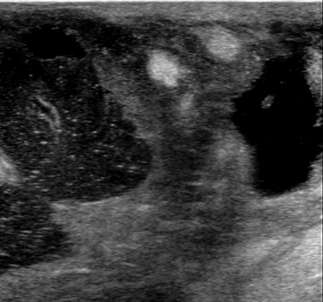

The ultrasound image above demonstrates sonographic architectural distortion. The hyperechoic (bright) bands of tissue interdigitating between the fat in the breast become focally altered and seem to radiate around a small lesion. Biopsy revealed a complex sclerosing lesion (sometimes called a radial scar) which is a benign, but sometimes high risk lesion, which can be recognized as architectural distortion on ultrasound. Other examples of benign causes of architectural distortion include sclerosing adenosis, fat necrosis, post-procedural changes, granular cell tumors, and breast fibromatosis. Architectural distortion may also be associated with breast cancer, as evidenced by the example below:

The above ultrasound demonstrates a hypoechoic (dark) mass with indistinct margins, posterior shadowing, and distortion of the normal breast tissue. This was biopsied, revealing invasive ductal carcinoma (IDC). Both ductal carcinoma in situ (DCIS) and IDC may result in distortion.